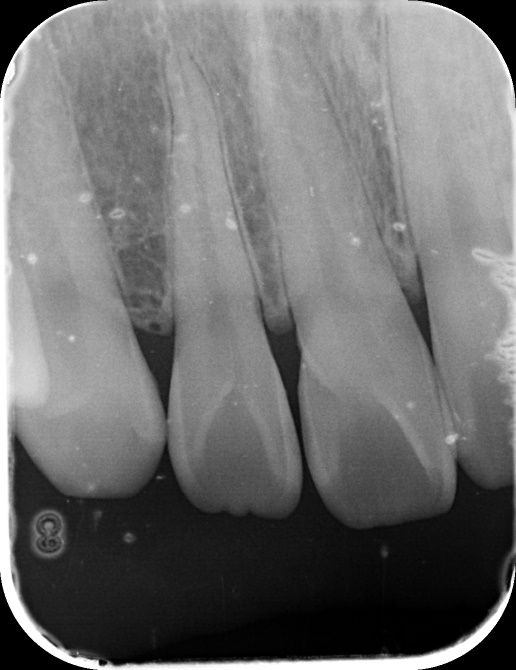

안녕하세요! 최근에 건강보험검진을 받으러가서 앞니 사이에 충치가 의심된다구 찍은 사진입니다.

1. 앞니에 충치가 있는건가요? (앞니 12, 11, 21, 22번 사이가 의심된다구 하셨습니다.)

• 2번 째 사진

엑스레이 사진상으로 보면 치아 사이에 작은 충치가 잇는것처럼 보이긴합니다. #11 12 사이 21 22사이는 사진상으로 보이는데 #11 21 사이는 사진상에 겹쳐보여 직접봐야 알수 잇을것같습니다.